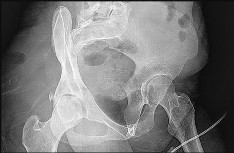

Question 2:

A 13-year-old obese male presents with acute-on-chronic hip and knee pain and an inability to bear weight on the affected limb. Radiographs confirm an unstable slipped capital femoral epiphysis (SCFE). He is taken to the operating room for urgent in-situ pinning. What is the most significant complication associated with attempting a forceful, intentional closed reduction of this deformity prior to hardware placement?

Correct Answer: Femoral head osteonecrosis (avascular necrosis)

Explanation:

An unstable SCFE (defined as the inability to bear weight even with crutches) already carries a high risk of osteonecrosis. Attempting a forceful closed reduction further disrupts the fragile retinacular vascular supply to the femoral epiphysis, significantly increasing the risk of iatrogenic avascular necrosis. Gentle reduction by positioning may occur naturally, but intentional forceful reduction is contraindicated.